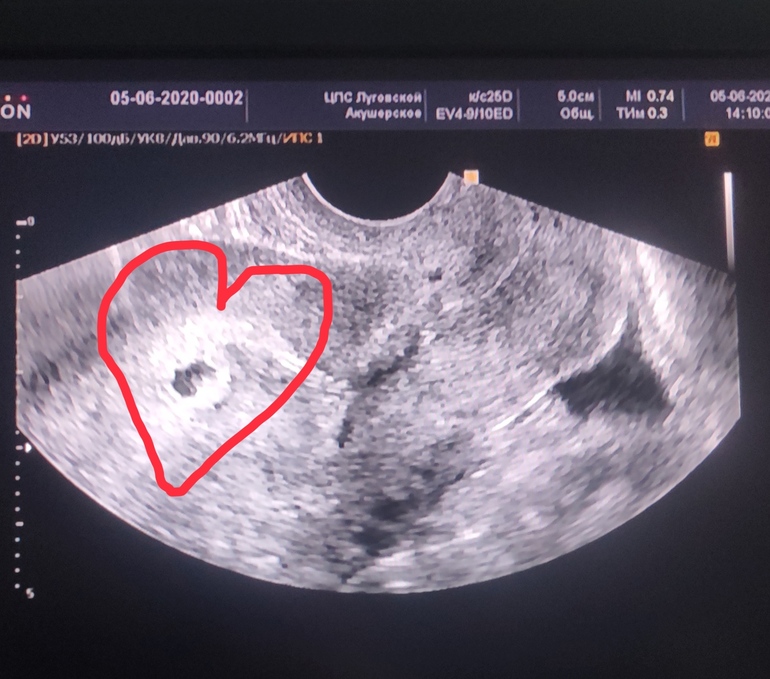

УЗИ сделала..

Плодное яйцо есть, соответствует сроку 5 недель..